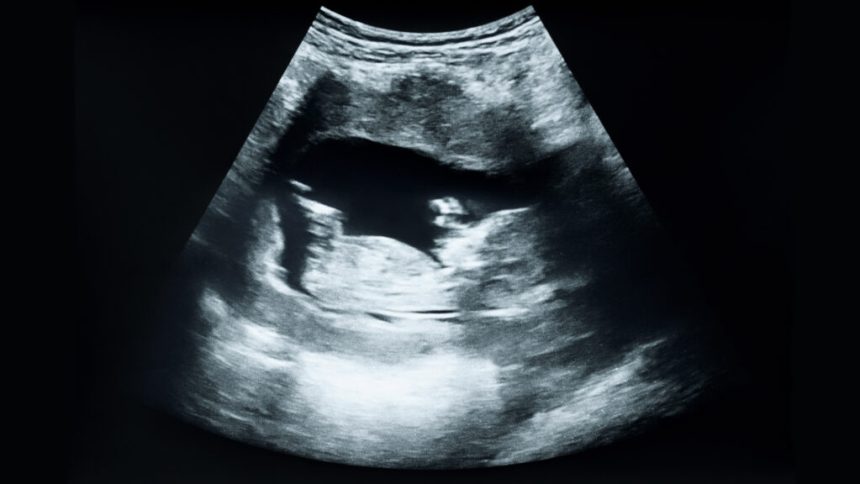

C-section Rate Reaches Decade High in 2025

The percentage of cesarean deliveries increased to 32.5% last year, marking the highest annual rate in the U.S. since 2013, as per new CDC data from the National Center for Health Statistics. Incremental increases in the C-section rate have been observed since 2020. Additionally, the rate for low-risk C-sections rose to 26.9%, the highest since 2012.

Megan Thielking previously noted that high C-section rates do not necessarily equate to better birth outcomes. Over a decade later, her insights remain relevant in understanding the current situation.

Additional CDC data reveals that there were over 3.6 million births in the U.S. last year, although this figure represents a 1% decrease from 2024. Notably, the birth rate for teenagers aged 15 to 19 saw a 7% decline.